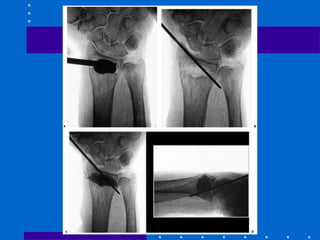

Pinagem e gesso

• Indicado para fraturas extra-articulares e

simples articulares

• 1º estilóide 2º coluna intemediária (fossa

lunar) de dorsal ulnar para proximal radial

3º fragmentos impactados podem ser

suportados por fios subcondrais transversais

Kapandji

• Fios intrafocais radial e dorsal servindo de

suporte

• Original 1 fio dorsal e 1 estilóide

• Modificada: 2 fios dorsais e 1 estilóide

• Tendência a translação do fragmento distal

• Efetivo para fraturas extra-articulares